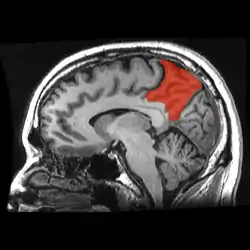

![]() Sagittal MRI slice with the precuneus shown in red. | |

Precuneus highlighted in green on sagittal T1 MRI images